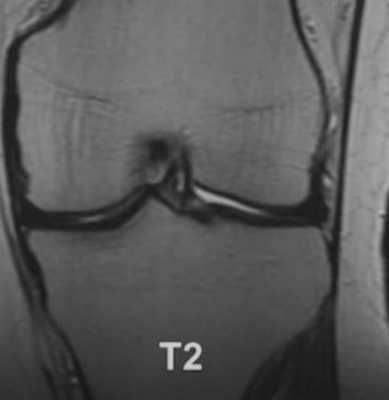

МР-снимок коленного сустава в режиме Т2, контузия кости

При МРТ получают серии монохромных снимков анатомической области в аксиальной, сагиттальной и фронтальной плоскостях. При изучении изображений врач видит контуры различных элементов сочленения. Расшифровка МРТ-снимка коленного сустава подразумевает оценку сканов в сравнении с нормой. МР-томограммы называют срезами, поскольку изображения производят послойно, с шагом 1-2 мм. Врач последовательно изучает анатомическую зону на предмет соответствия всех структур норме. В процессе расшифровки фото обращают внимание на качество визуализации элементов, четкость контуров, присутствие зон измененного МР-сигнала (гипер- или гипоинтенсивного) в различных режимах сканирования (Т1 ВИ, Т2 ВИ, ДВИ, подавление жира).